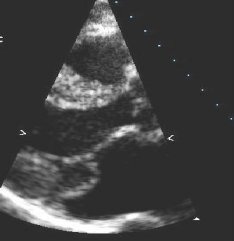

Prolapso do folheto P2 da valva mitral: visualização 2D

Do acervo de Prakash P. Punjabi